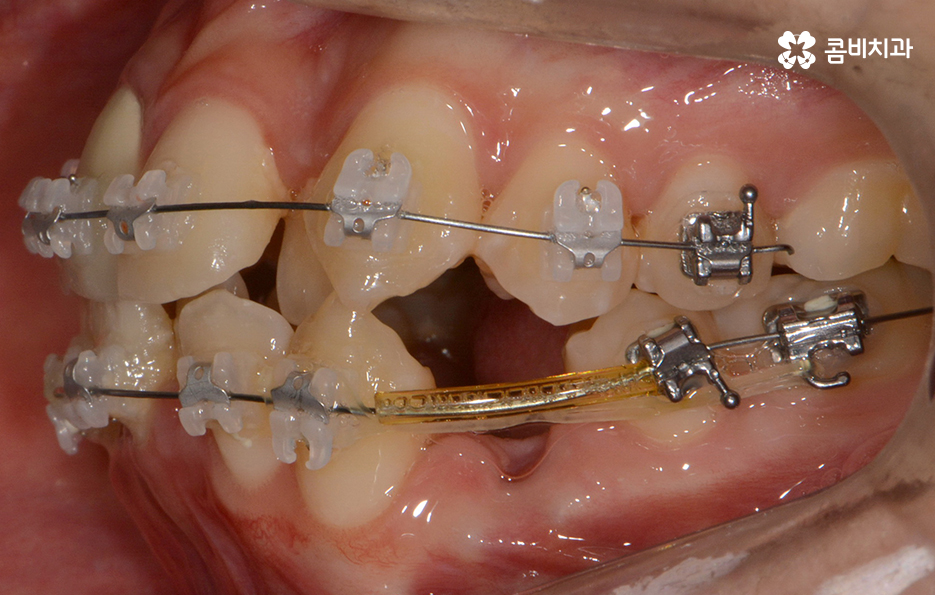

위 환자분의 케이스는 아랫니에 치아 2개를 발치하여

치아의 이동 공간을 확보하였고 발치교정이 진행될 때는

윗니와 아랫니 각각 2개씩 발치를 하는 경우가 많지만

위 사례는 치열, 교합 등을 고려할 때 아랫니 2개만

발치가 진행되었던 경우라고 볼 수 있어요.

왼쪽이 윗니이고 오른쪽이 아랫니인데 치열의 불규칙함이

심한 편이다 보니 평소 음식물이나 치석이 끼기 쉬운 환경이

되고 이러한 구강 환경이 지속된다면 충치와 잇몸질환의 발생률이 높아질 수 있어요.